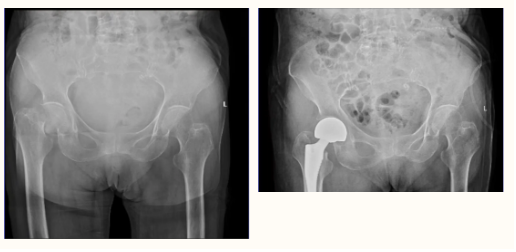

近日,隨州市中心醫(yī)院龍門院區(qū)創(chuàng)傷外科成功為一例高齡老人實(shí)施股骨頸關(guān)節(jié)置換術(shù),手術(shù)順利完成,患者現(xiàn)已下地走路,恢復(fù)良好。像這類年齡大、風(fēng)險高的手術(shù)已經(jīng)是創(chuàng)傷外科的常態(tài)化手術(shù)。 目前老太太身體狀況恢復(fù) ...